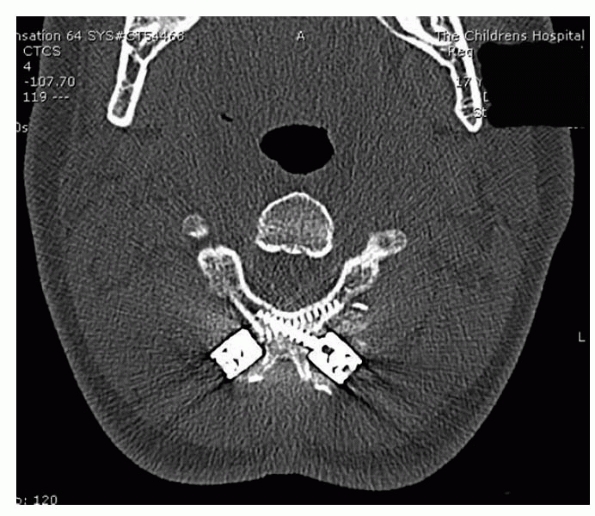

special attention because of the dangers of inadvertent skull

penetration with a pin. CT scanning before halo application aids in

determining bone structure and skull thickness. It also aids in

determining whether or not cranial suture interdigitation is complete

and if the fontanels are closed. The thickness of the skull varies

greatly up to 6 years of age and is not similar to that of adults until

the age of 16 years.134 Garfin et al.74

evaluated the pediatric cranium by CT and determined that the skull is

thickest anterolaterally and posterolaterally, making these the optimal

sites for pin placement.

insertion torques used in younger children also deserve special

mention. The placement of pins at the torque pressures used in adults

will lead to penetration during insertion.134

Pins should be inserted at torques of 2- to 4-inch pounds; however, the

variability and reliability of pressures found with various torque

wrenches during cadaver testing are great, and each pin must be

inserted cautiously.46 The use of 8

to 12 pins inserted at lower torque pressures aids in obtaining a

stable ring with less chance of inadvertent penetration (Fig. 18-17).

The insertion of each pin perpendicular to the skull also improves the

pin-bone interface and the overall strength of the construct.47